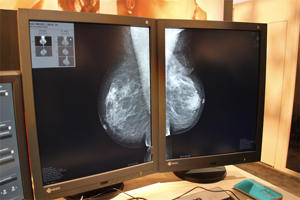

FUJIFILM Medical Systems(富士フイルムメディカル)では,マンモグラフィの読影端末として,新しいマンモグラフィワークステーションである「AMULET Bellus(ベラス)」(日本国内の薬事承認済)を展示した。

「AMULET Bellus」はビューワとレポートシステムから構成され,特長としては富士フイルムの画像認識技術を生かしたシェーマの自動作成機能や高速経時差分機能,容量の大きいマンモ画像の高速表示,直感的なユーザーインターフェイス,柔軟なカスタマイズ可能なレポートシステムなどを提供する。同じソフトウエアで,ライセンスキーを切り替えることで,2Dとリアル3D Mammographyをハンドリングできる。

「AMULET Bellus」の高速経時差分機能は,マンモの読影で重要な比較読影の際に,左右や過去と現在など2枚の画像を1つの画面上で高速に切り替えることで,目線を移動させることなく画像の変化をとらえることができる表示方法である。変化したところに反応する,人間の視覚の残像効果を生かした読影法と言えるだろう。画像を切替えながら,ズームや移動,ウィンドウレベルの変更もスムーズに行える。マンモグラフィの画像は1枚の容量が大きいため,これまで画像の読み込みや表示に時間がかかっていたが,GPU(グラフィックボード)を生かした高速画像処理によってこれを解決した。